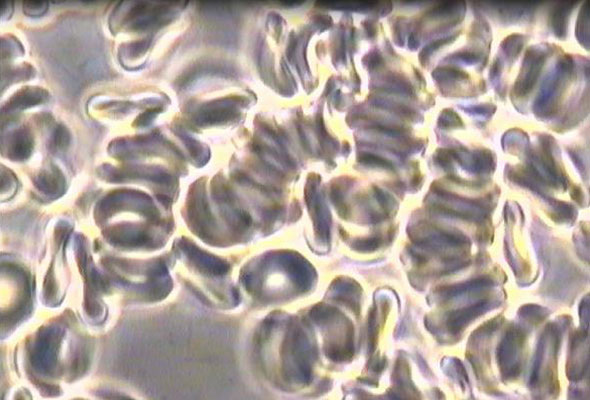

These included complete reversals in conditions such as tendinopathy, osteoporosis (OP), chondromalacia patellae (CMP), hypertension (HTN), pre-diabetes, chronic fatigue syndrome (CFS), osteoarthritis (OA), degenerative disc disease (DDD), cellular agglutination, urinary tract infections (UTI), and stage-3 chronic kidney disease (CKD3). The regenerative results were often accompanied with supportive medical documentary evidence.

In 2012, Creed disclosed his microscopic before/after blood analyses to the Human Performance Laboratory of the Naval Special Warfare (NSW) Group 2 Training Detachment (TRADET) and revealed definitive proof of the adverse agglutinating effects of gluten on red blood cells.

Before-and-after images of Creed’s red blood cells in response to specific dietary changes